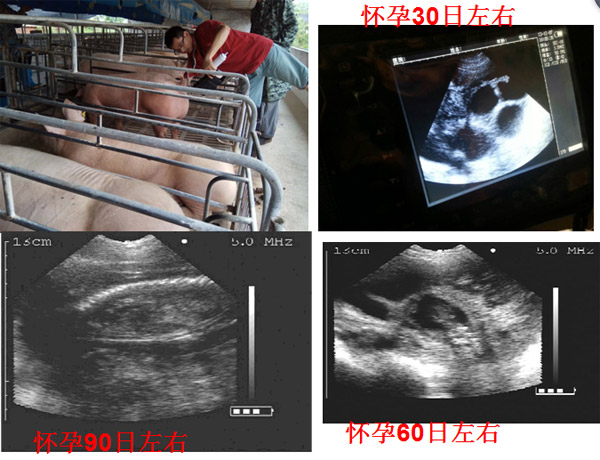

??????????????????????С????????????????????????????????????????B?????????????????????????B??????й????????????????????????????????????????????????????????“Χ????”??????????????

????????????????????????????????????????????????????????С??????μ?????????B????????????????????????????????????????仳?????????????????????“Χ????”???????????????????????????????????????????????????????????